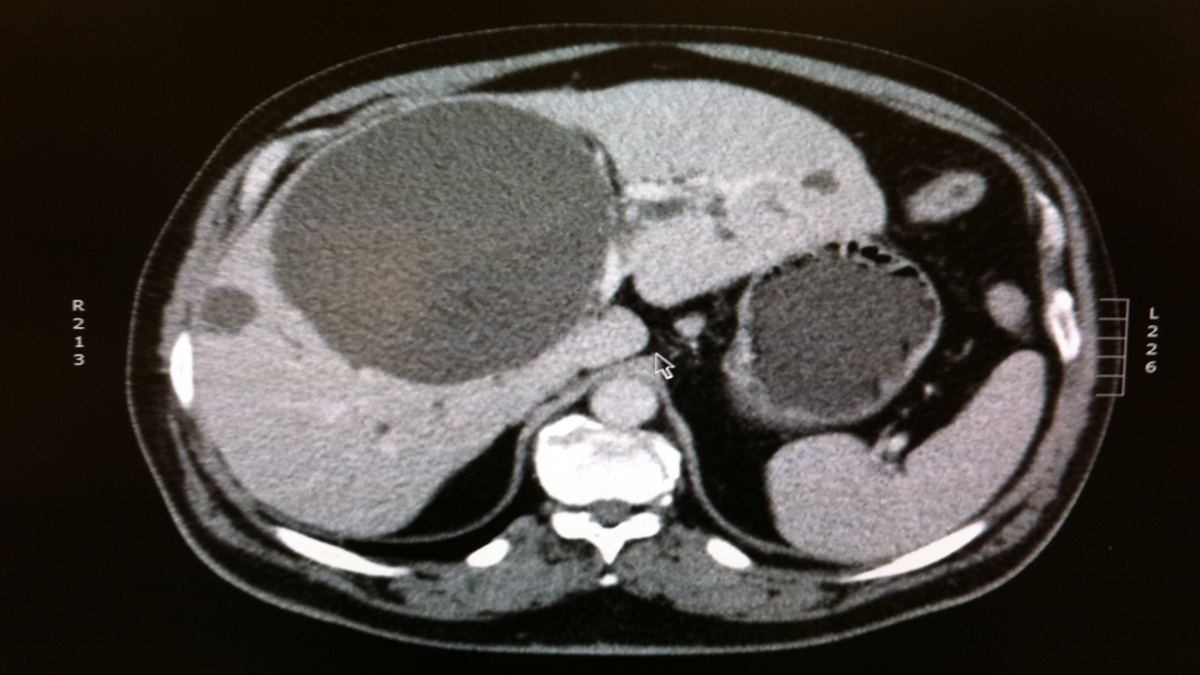

A 67-year-old man with history of hepatitis C cirrhosis sees you after recent presentation in emergency department with abdominal pain 5 years after achieving sustained virological response (SVR). Unfortunately, he was lost to follow-up after achieving SVR so he had not been undergoing hepatocellular carcinoma (HCC) surveillance. He underwent CT imaging in the emergency department, which demonstrated a large liver mass. He subsequently underwent a diagnostic MRI of the abdomen, which showed a large liver mass in the right lobe with arterial enhancement and delayed washout, including evidence of vascular invasion (LR-TIV) [figures A and B]. His chest CT done at that time showed evidence of pulmonary metastases. His liver function remains preserved after achieving SVR, with no history of ascites or hepatic encephalopathy. Laboratory test results demonstrate bilirubin 0.9 mg/dL (normal: 0.3-1.2 mg/dL), albumin 3.7 g/dL (normal: 3.5-5.5 g/dL), and INR 1.1 (normal: <1.4). Platelet count is 147,000/µL (normal: 150,000-350,000/µL). What would be the recommended management strategy for this patient?

This patient was found to have definite HCC with evidence of vascular invasion (LR-TIV). This patient has advanced-stage HCC (Barcelona Clinic Liver Cancer stage C) in the setting of compensated cirrhosis. Patients with advanced-stage HCC are not eligible for surgical or locoregional therapies in most cases and should be referred for systemic therapy. Although tyrosine-kinase inhibitors (TKIs) can be used, the IMBrave150 trial recently demonstrated superiority of atezolizumab/bevacizumab as first-line therapy for these patients. Given the risk of bleeding in the setting of HCC and with use of bevacizumab, patients should undergo an EGD to confirm that they have a low risk of bleeding prior to treatment initiation.